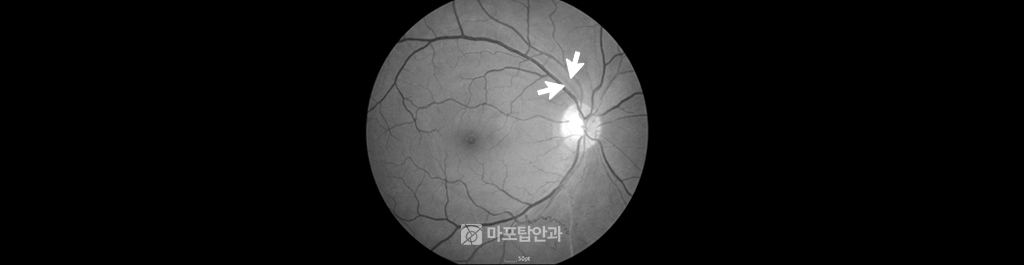

40세 남자환자의 안저 검진 사진입니다. 건강 검진상으로는 정상이었으나 상이측 시신경섬유결손과 시야손상 발견되어 초기 녹내장 진단 받고 치료 중입니다.